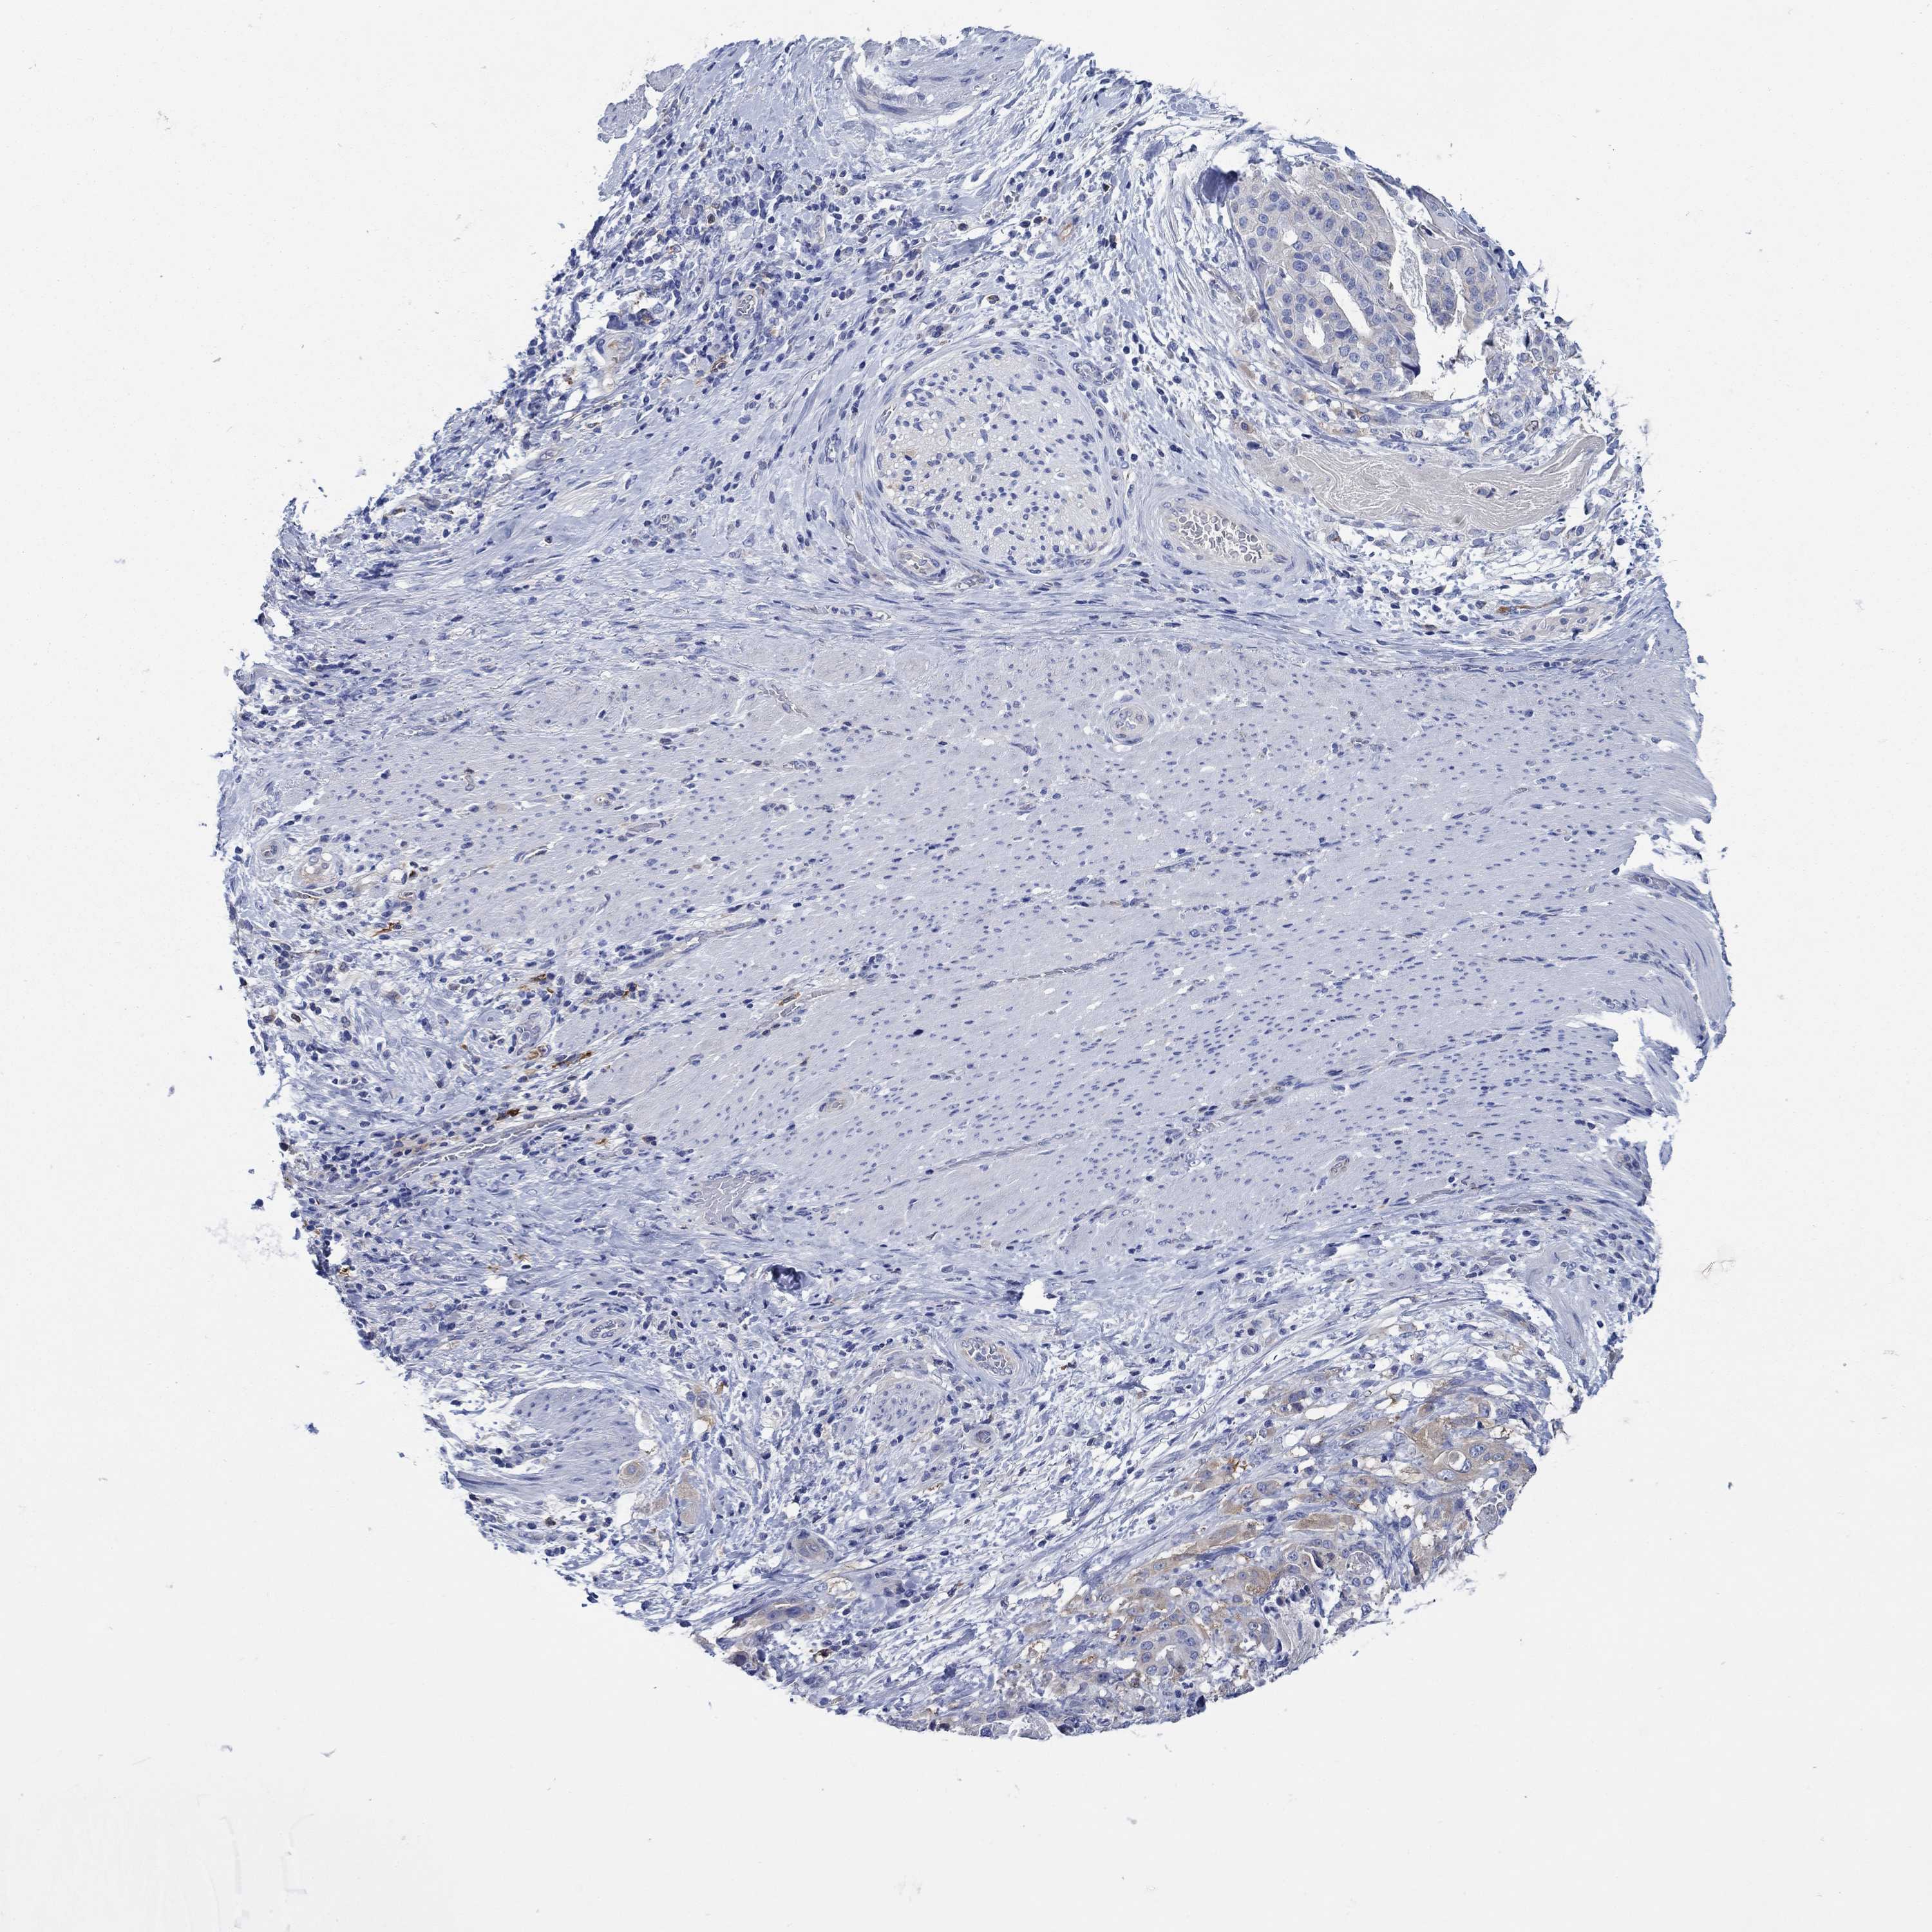

STOMACH CANCER - Protein expressioni

A mouse-over function shows sample information and annotation data. Click on an image to view it in a full screen mode. Samples can be filtered based on level of antibody staining by selecting one or several of the following categories: high, medium, low and not detected. The assay and annotation is described here.

Antibody stainingi

Antibody staining in the annotated cell types in the current human tissue is reported as not detected, low, medium, or high, based on conventional immunohistochemistry profiling in selected tissues. This score is based on the combination of the staining intensity and fraction of stained cells.

Each image is clickable and will lead to virtual microscopy that enables deeper exploration of all samples and also displays staining intensity scores, fraction scores and subcellular localization as well as patient and tissue information for each sample.

Antibody HPA023623

Antibody HPA066431

Staining

High

Medium

Low

Not detected

Intensity

Strong

Moderate

Weak

Negative

Quantity

>75%

75%-25%

<25%

None

Location

Nuclear

Cytoplasmic/membranous

Cytoplasmic/membranous,nuclear

Adenocarcinoma, NOS

Adenocarcinoma, High grade